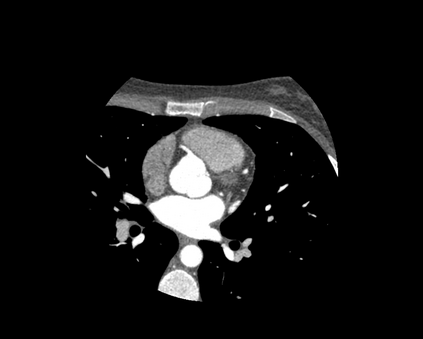

The standard non-invasive imaging technique used to assess the severity and extent of Coronary Artery Disease (CAD) is Coronary Computed Tomography Angiography (CCTA). However, manual grading of each patient's CCTA according to the CAD-Reporting and Data System (CAD-RADS) scoring is time-consuming and operator-dependent, especially in borderline cases. This work proposes a fully automated, and visually explainable, deep learning pipeline to be used as a decision support system for the CAD screening procedure. The pipeline performs two classification tasks: firstly, identifying patients who require further clinical investigations and secondly, classifying patients into subgroups based on the degree of stenosis, according to commonly used CAD-RADS thresholds. The pipeline pre-processes multiplanar projections of the coronary arteries, extracted from the original CCTAs, and classifies them using a fine-tuned Multi-Axis Vision Transformer architecture. With the aim of emulating the current clinical practice, the model is trained to assign a per-patient score by stacking the bi-dimensional longitudinal cross-sections of the three main coronary arteries along channel dimension. Furthermore, it generates visually interpretable maps to assess the reliability of the predictions. When run on a database of 1873 three-channel images of 253 patients collected at the Monzino Cardiology Center in Milan, the pipeline obtained an AUC of 0.87 and 0.93 for the two classification tasks, respectively. According to our knowledge, this is the first model trained to assign CAD-RADS scores learning solely from patient scores and not requiring finer imaging annotation steps that are not part of the clinical routine.